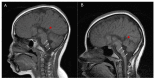

The EARS2 nuclear gene encodes mitochondrial glutamyl-tRNA synthetase, a member of the class I family of aminoacyl-tRNA synthetases (aaRSs) that plays a crucial role in mitochondrial protein biosynthesis by catalyzing the charging of glutamate to mitochondrial tRNA(Glu). Pathogenic EARS2 variants have been associated with a rare mitochondrial disorder known as leukoencephalopathy with thalamus and brainstem involvement and high lactate (LTBL). The targeted sequencing of 150 nuclear genes encoding respiratory chain complex subunits and proteins implicated in the oxidative phosphorylation (OXPHOS) function was performed. The oxygen consumption rate (OCR), and the extracellular acidification rate (ECAR), were measured. The enzymatic activities of Complexes I-V were analyzed spectrophotometrically. We describe a patient carrying two heterozygous EARS2 variants, c.376C>T (p.Gln126*) and c.670G>A (p.Gly224Ser), with infantile-onset disease and a severe clinical presentation. We demonstrate a clear defect in mitochondrial function in the patient's fibroblasts, suggesting the molecular mechanism underlying the pathogenicity of these EARS2 variants. Experimental validation using patient-derived fibroblasts allowed an accurate characterization of the disease-causing variants, and by comparing our patient's clinical presentation with that of previously reported cases, new clinical and radiological features of LTBL were identified, expanding the clinical spectrum of this disease.